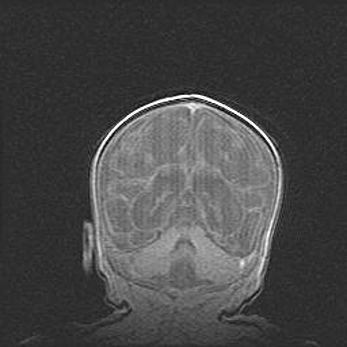

Открытая гидроцефалия.

Возраст: 6 месяцев 15 дней

Вес: 6200 г

Пол: женский

Окружность головы: 41 см

Срок гестации: 38 недель

Гидроцефалия головного мозга у новорожденных – это скопление избыточного количества цереброспинальной жидкости в головном мозге. Ее избыточное скопление в мозге приводит к патологическому расширению желудочков мозга (четырех полостей, расположенных в глубине белого вещества мозга, заполненных цереброспинальной жидкостью и связанных узкими проходами).

Открытый тип гидроцефалии (сообщающаяся) наблюдается тогда, когда нарушен механизм всасывания ликвора в системный кровоток. При этом типе причиной заболевания чаще всего является перенесенные ранее инфекции (например: менингит),  либо же наличие крови в субарахноидальном пространстве.